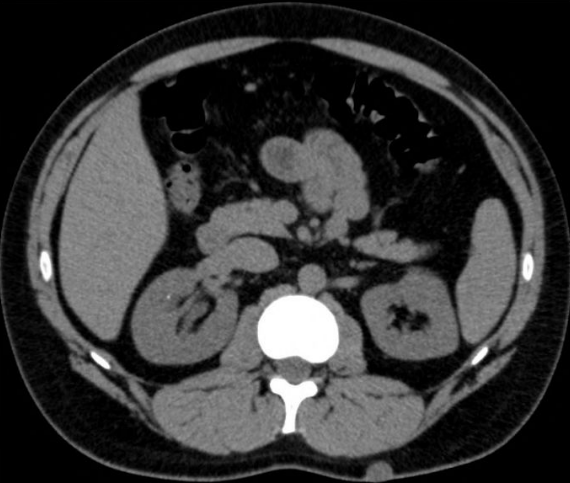

Visualização anatômica do abdômen em tomografia computadorizada (Fonte: Radiology Key)